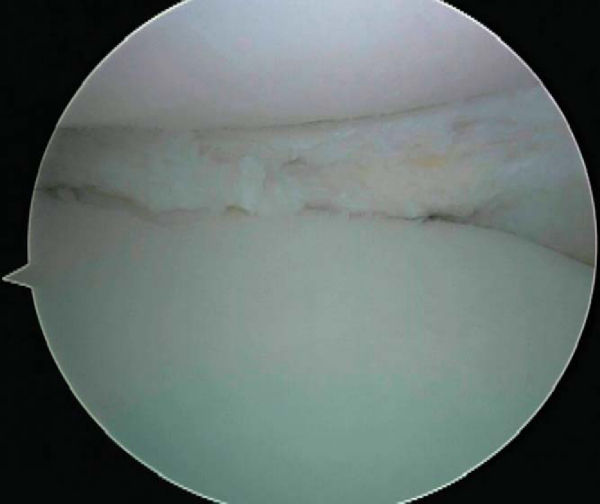

2. Preparation of Meniscal Rim

The involved posterior horns of the native menisci are trimmed to provide a bleeding surface that will support allograft healing. We prefer a 1- to 2-mm rim because this gives the sutures a more stable platform to fix the allograft. The anterior and posterior horn attachments are identified and marked. Care should be taken to maintain these anatomic landmarks (when available) because they help configure tunnel placement (

Fig. 50-4

).